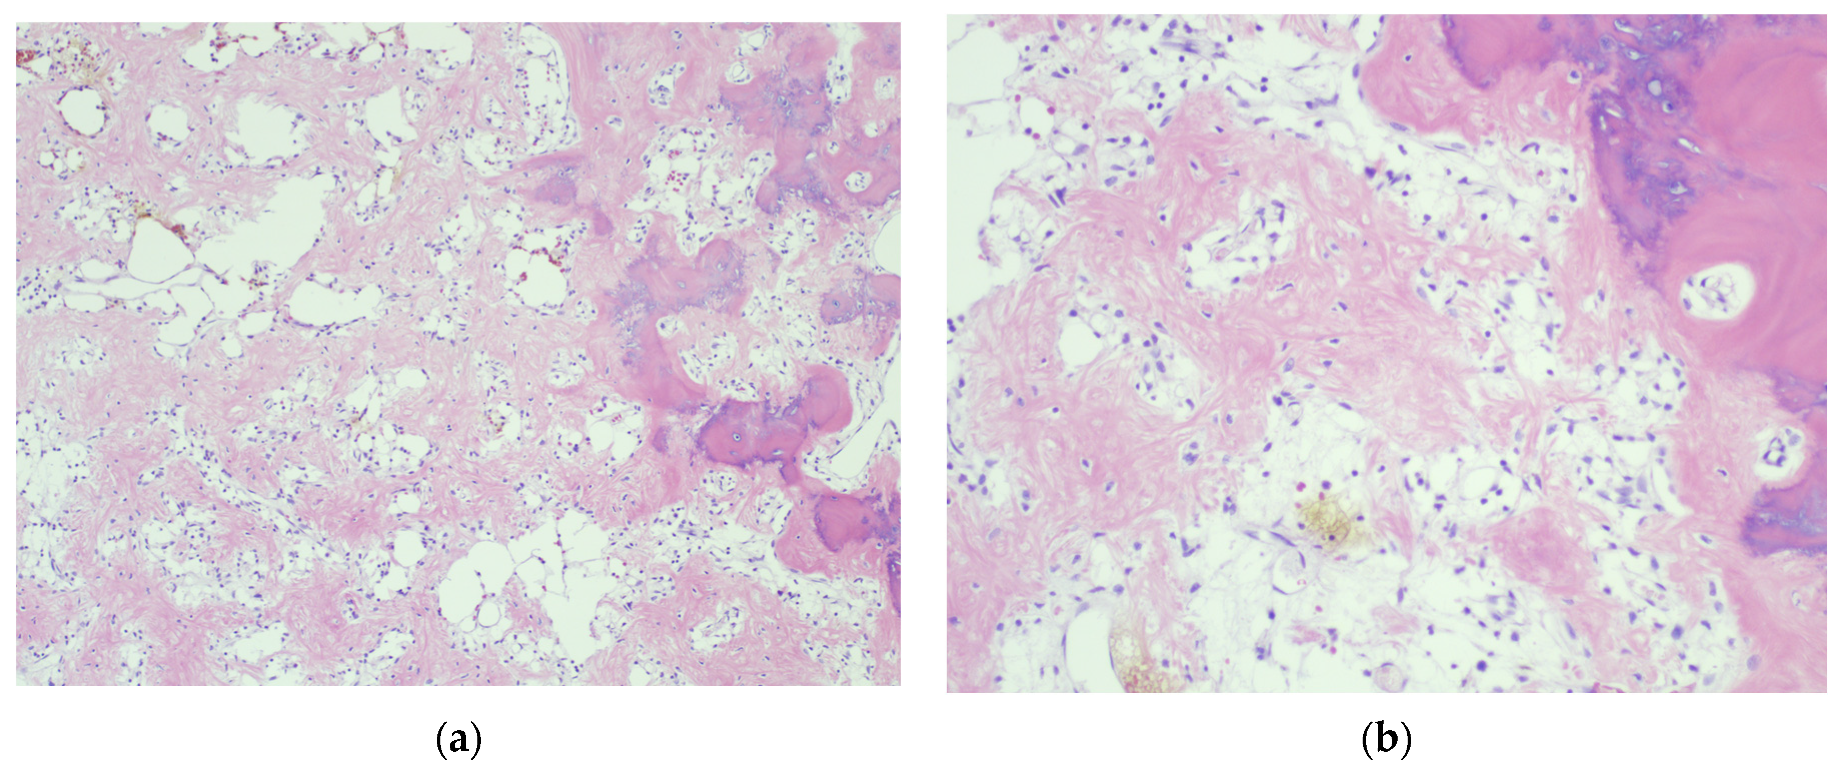

4.3. Final Diagnosis